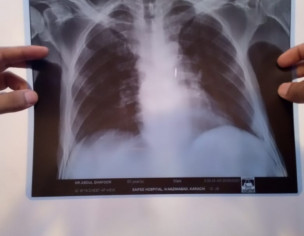

Patient was admitted in hospital due to cancer illness. He didnt have any fever or cough. The doctors performed chest X ray and determined on basis of X ray that patient has contracted coronavirus. I have attached the pictures of the X ray. Please verify if lungs are clear or not.

If they are suspecting corona ask them to do PCR test. X-ray chest is not specific for Covid. CT chest with contrast will clear the quirey

Do pcr test for Corona

Xray chest is not specifically finded Corona

Pcr will tells u actually current status of Corona thanks